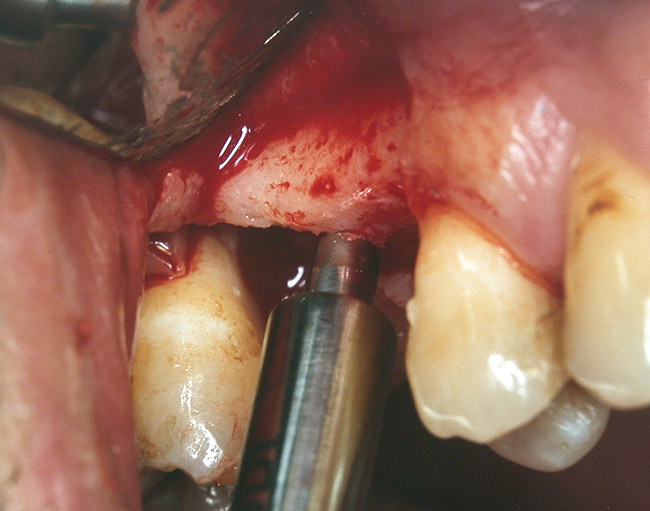

Case 2

A 55-year-old male was referred for implant placement and prosthetic rehabilitation in the area of tooth No. 15. The tooth had been extracted 4 years prior. The radiograph revealed inadequate bone height for implant positioning (Figure 6). It was decided to insert an implant that was 11.5 mm in length and 3.75 mm in diameter, performing a slight osteotomic maxillary sinus lift. A heterologous bone graft also was planned to obtain a larger sinus lift.

A full-thickness mucoperiosteal flap was raised, and alternating osteotomes were used to prepare the implant site. After achieving a length of 7 mm (Figure 7A and Figure 7B), heterologous bone graft was implanted and the osteotome sequence was repeated. The implant showed primary stability.

Figure 7A and Figure 7B Alternating osteotomes with variable conicity used to perform the alveolar remodeling in the area of tooth No. 15.

Figure 7a  Alternating osteotomes with variable conicity used to perform the alveolar remodeling in the area of tooth No. 15.

Figure 7a

Figure 7b  Alternating osteotomes with variable conicity used to perform the alveolar remodeling in the area of tooth No. 15.

Figure 7b